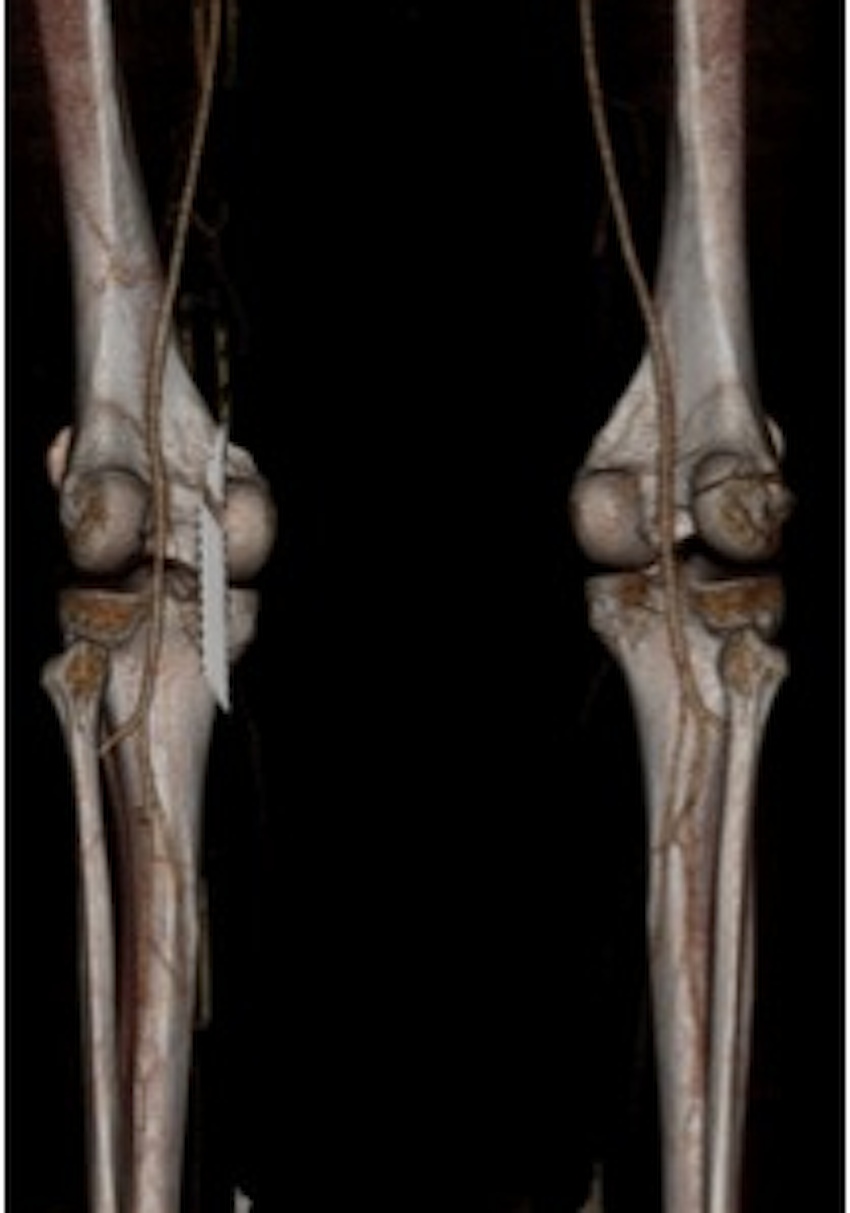

Tibial plateau fractures

CT demonstrating medial tibial plateau in setting of knee dislocation and posterolateral corner injury